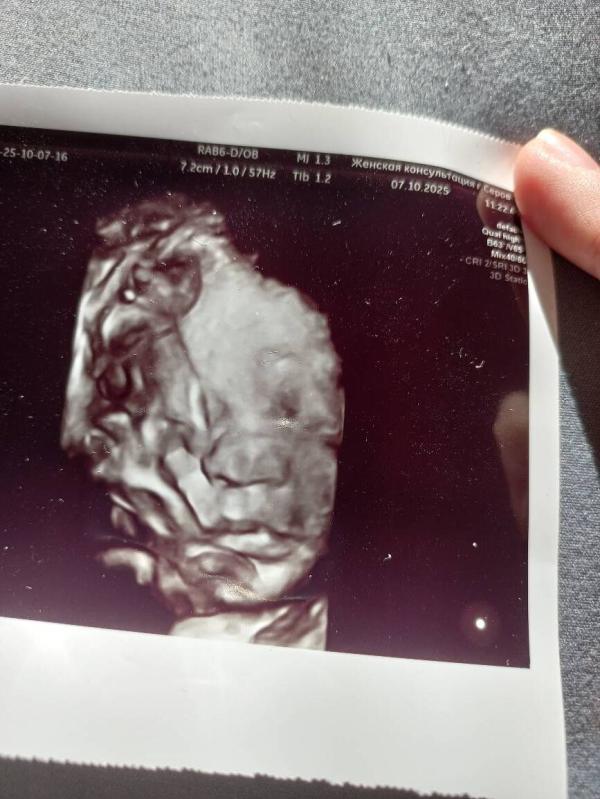

35 недель.🥳

Сегодня прошла третий скрининг. Пупс весит 2300, набрал полкило за 3 недели.🤭

Как бы хотелось родить через пару неделек уже.🤭 Очень интересно посмотреть, как сыночек будет выглядеть, хоть уже сейчас вижу, что на папу похож.